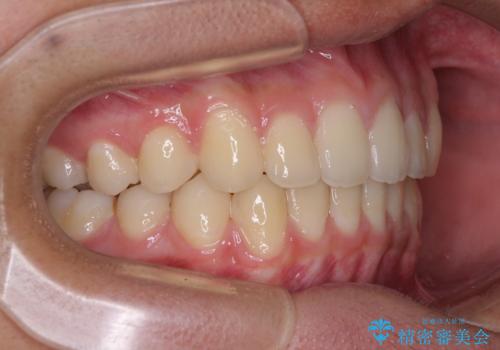

- 前歯のデコボコと隙間を気にして来院された高校生の患者様です。

下顎前歯が上顎前歯を突き上げるような咬み合わせとなっており、その影響で上顎正中に隙間ができている状態でした。

叢生の程度は軽度であり、本人もしっかりと使用する自信があるとのことだったので、インビザラインによる矯正治療を行うこととしました。

突き上げによる隙間を予防する為に、深い咬み合わせを改善するような治療計画としました。咬み合わせを改善させることはできましたが、隙間は後戻りしやすいので、通常の下顎前歯のみではなく、上顎前歯2本もワイヤーで保定を行いました。